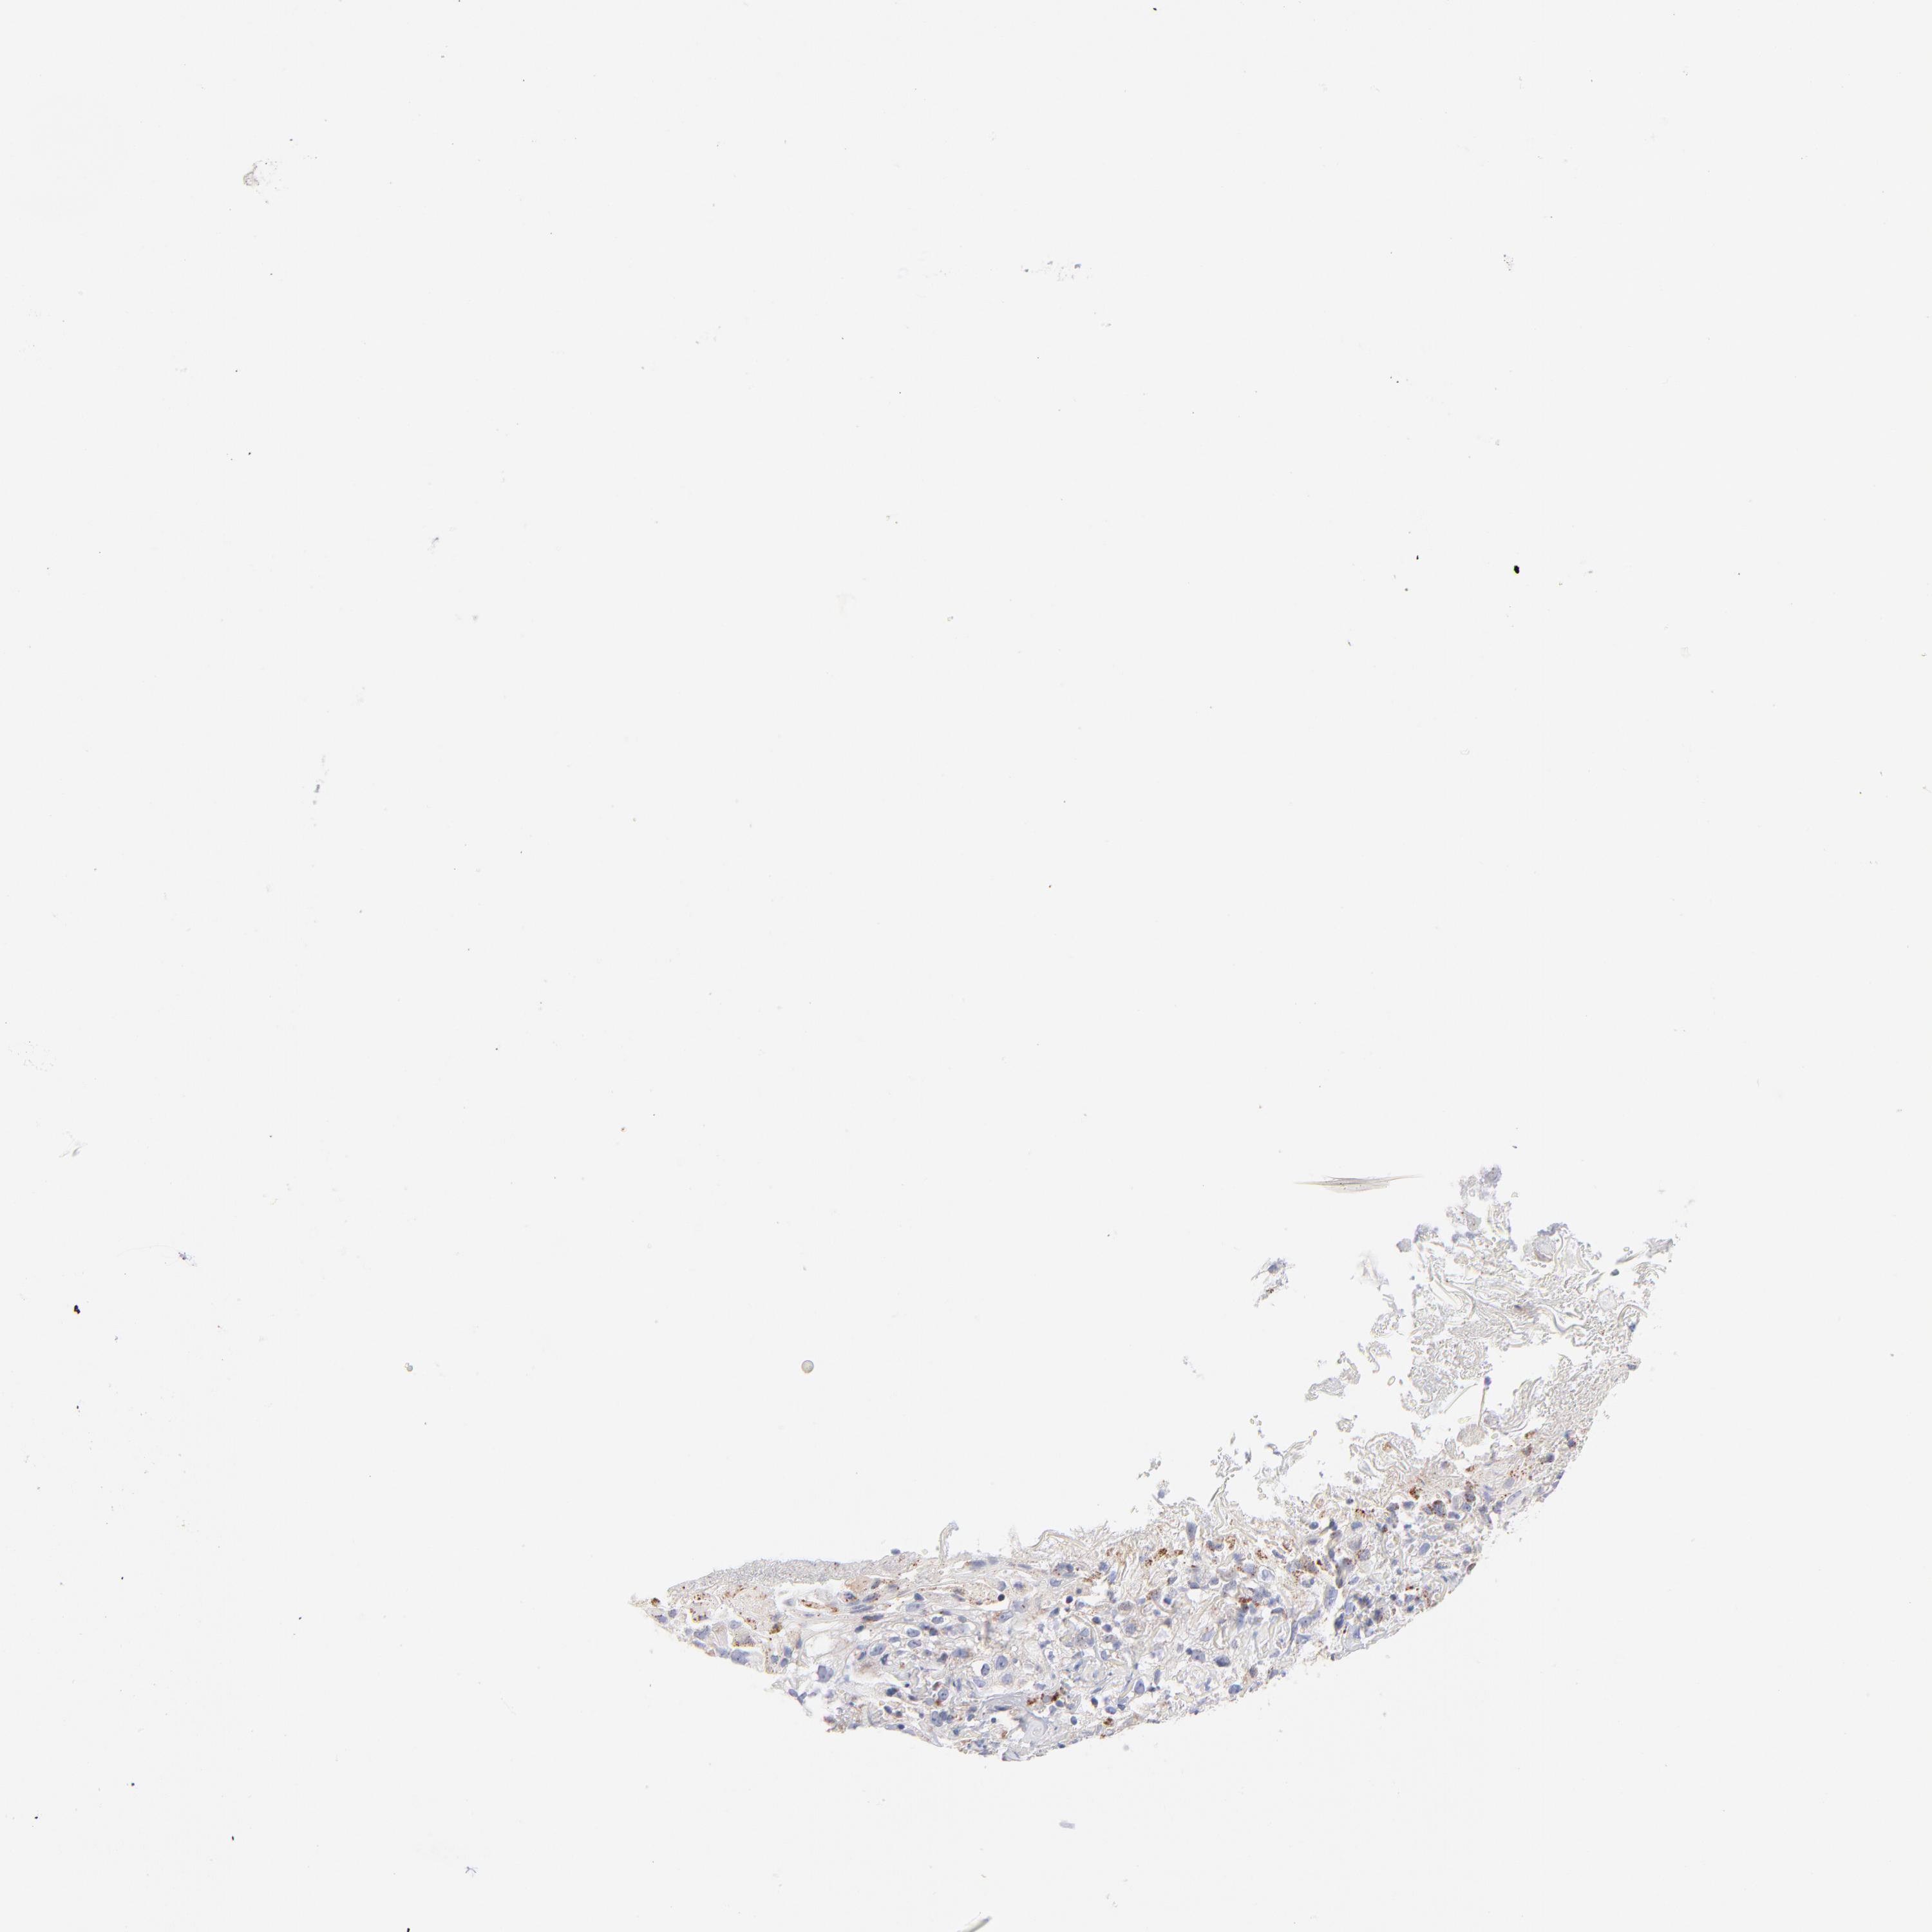

Basal cell and squamous cell cancer

SKIN CANCER - Protein expressioni

A mouse-over function shows sample information and annotation data. Click on an image to view it in a full screen mode. Samples can be filtered based on level of antibody staining by selecting one or several of the following categories: high, medium, low and not detected. The assay and annotation is described here.

Each image is clickable and will lead to virtual microscopy that enables deeper exploration of all samples and also displays staining intensity scores, fraction scores and subcellular localization as well as patient and tissue information for each sample.

Antibody HPA040786

Antibody CAB003782

Squamous cell carcinoma, NOS

Squamous cell carcinoma, metastatic, NOS